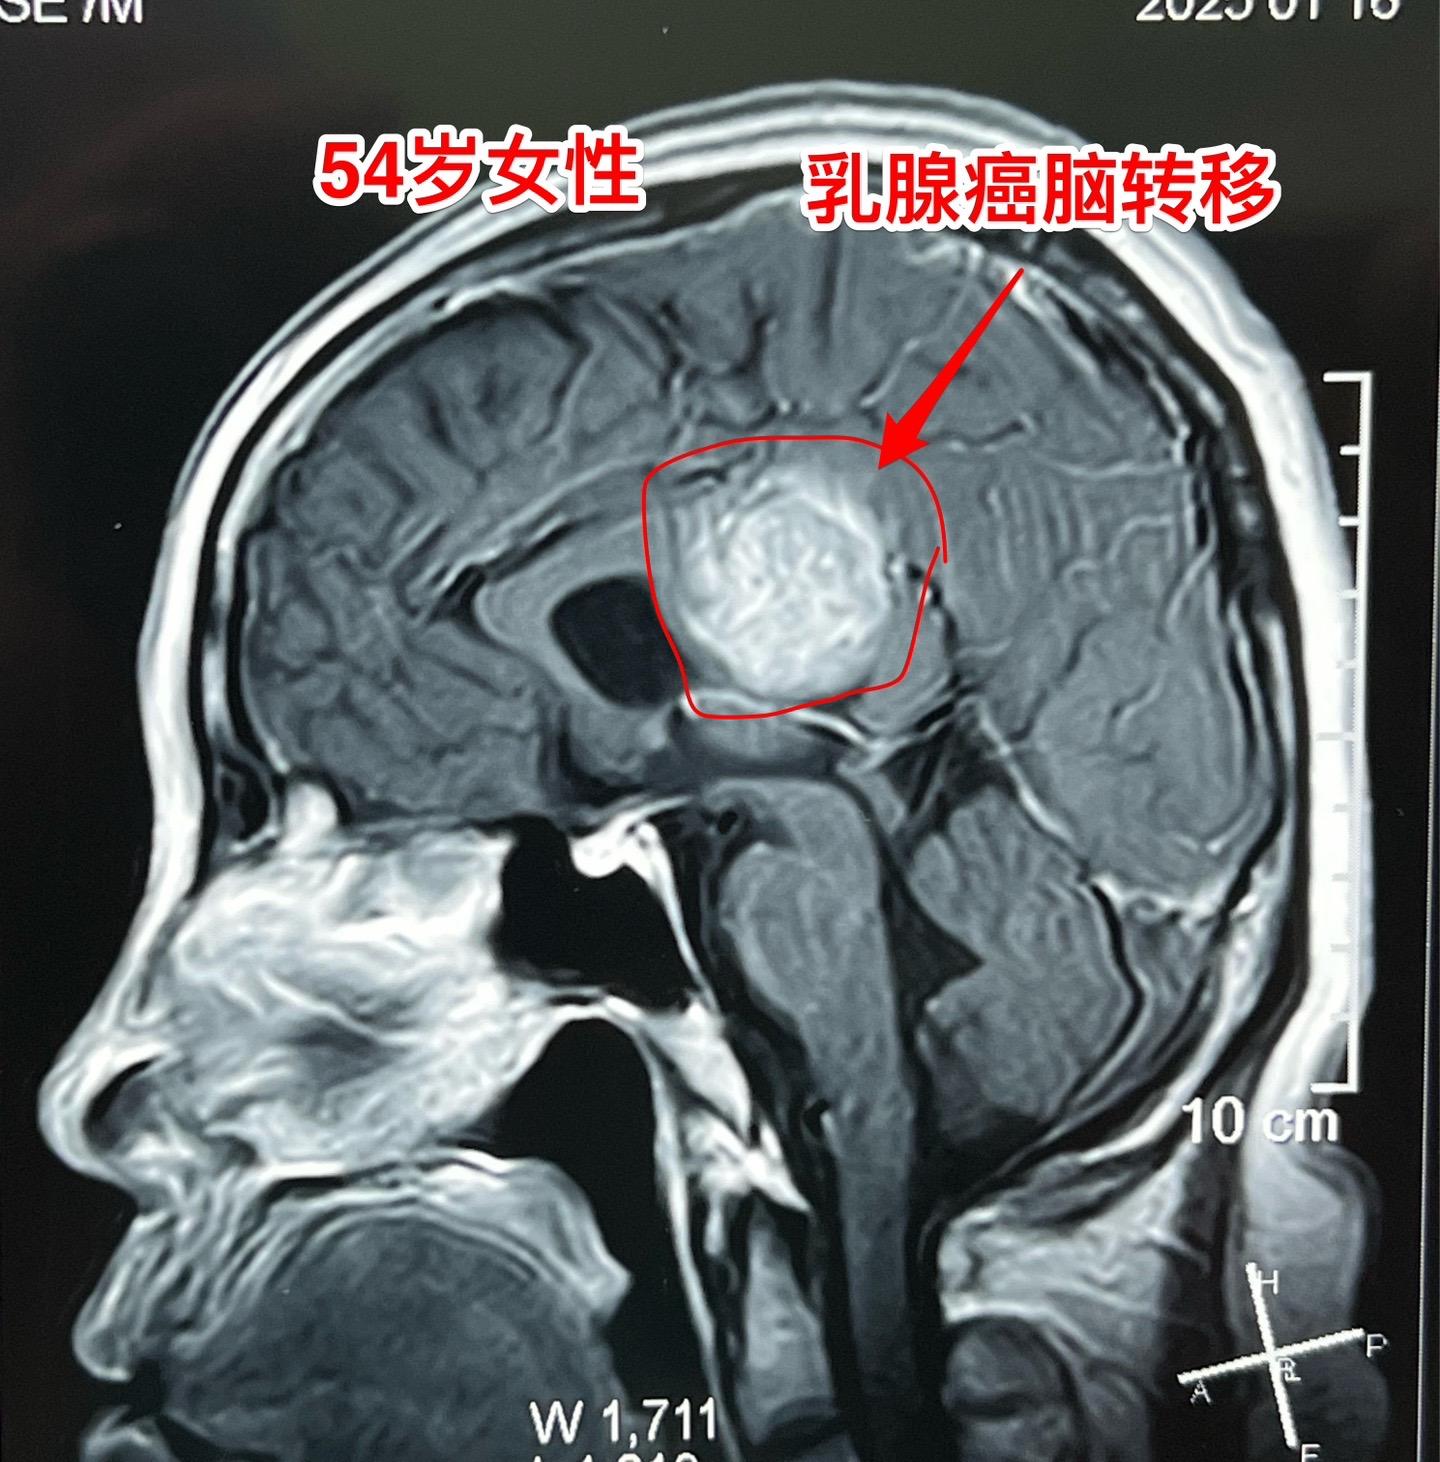

乳腺癌也能转移到脑部。脑部的转移瘤约80%来源于肺癌,绝大多数是腺癌。 乳腺癌发病率虽然低于肺癌,但也很常见。乳腺癌也可能转移到脑部。 这个54岁女性在7个月前先发现 脑部有个瘤,随后发现了乳腺癌,作了乳腺癌切除手术及内分泌治疗。多次复查磁共振显示脑部的瘤体积在增大,而且病人也出现头痛症状,故来作手术。 1月23日作了手术,顺利切除肿瘤。术前病人担忧出现偏瘫症状,手术后并没有出现。 针对这个病随后还需要综合治疗。